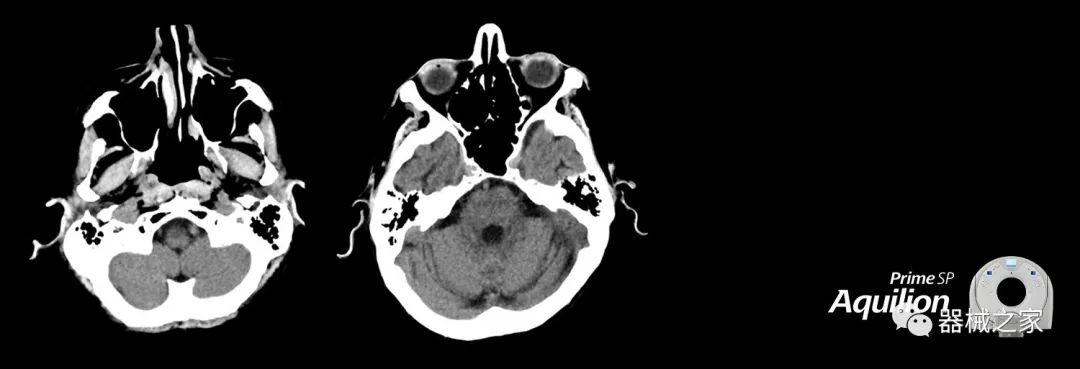

在以患者為中心的放射腫瘤學(xué)領(lǐng)域,計算機(jī)斷層掃描(CT)的可訪問性,可重復(fù)性和靈活性至關(guān)重要。為了建立這些價值,佳能醫(yī)療系統(tǒng)美國公司現(xiàn)在正在擴(kuò)大其放射腫瘤學(xué)CT模擬產(chǎn)品,包括Aquilion Prime SP和Aquilion Lightning 80高級CT系統(tǒng)。除了Aquilion LB之外,Aquilion Prime SP和Aquilion Lightning 80現(xiàn)在還包括放射治療(RT)選項,可為腫瘤學(xué)規(guī)劃提供高質(zhì)量的CT成像和精密工具。

擴(kuò)展視野(EFOV)可以看到更多的解剖結(jié)構(gòu)。Aquilion LB采用85 cm EFOV,而Aquilion Prime SP和Aquilion Lightning 70采用70 cm EFOV。

Aquilion Prime SP使設(shè)施能夠處理具有挑戰(zhàn)性的案例,同時為員工提供快速,靈活和高效的解決方案。